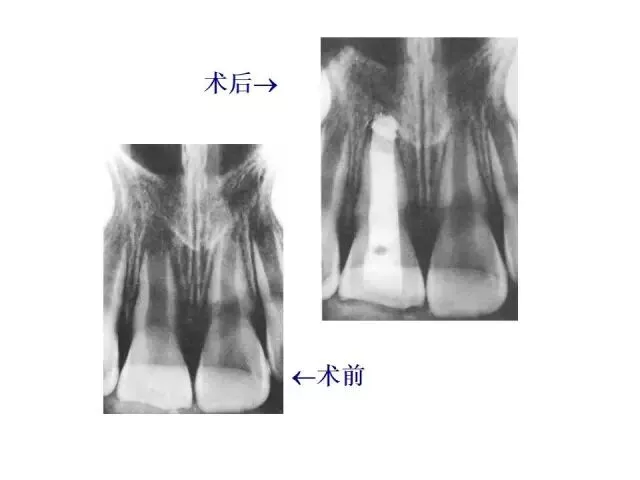

>PPT典藏 | 根尖诱导成型术

PPT典藏 | 根尖诱导成型术